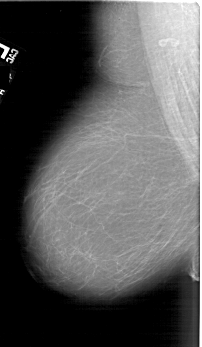

A_1798_1.LEFT_MLO

LEFT_MLO LINES 6241 PIXELS_PER_LINE 3631 BITS_PER_PIXEL 12 RESOLUTION 43.5 NON_OVERLAY